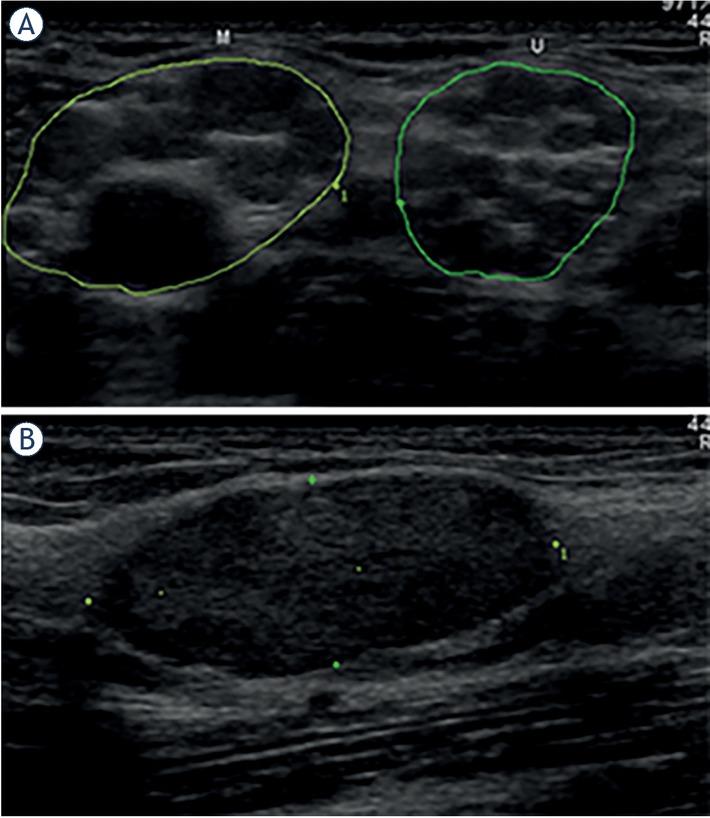

Morphological features of peripheral nerve tumors (PNTs) found on ultrasonographic (US) examination5 of individual patients

| # | Ratio | Shape | Contour | Encapsulation | Echo texture | Nerve position | Nerve transition | Number | Tumor diagnosis |

|---|---|---|---|---|---|---|---|---|---|

| 1 | 5 | Fusiform | Lobulated | Partial | Heterogeneous | Central | Infiltrative | Single | Neurofibroma |

| 2 | ? | Lobulated | Partial | Heterogeneous | ? | ? | Several | Schwannoma* | |

| 3 | 6 | Fusiform | Smooth | Whole | Heterogeneous | Central | Poorly defined | Single | Schwannoma |

| 4 | 6 | Fusiform | Fusiform | None | Heterogeneous | Central | Infiltrative | Several | Neurofibroma |

| 5 | 8 | Fusiform | Lobulated | Partial | Heterogeneous | Central | Infiltrative | Single | Perineurioma |

| 6 | > 10 | Fusiform | Lobulated | Partial | Heterogeneous | ? | ? | Single | Perineurioma |

| 7 | 6 | Fusiform | Smooth | None | Homogenous | Central | Infiltrative | Single | Perineurioma |

| 8 | 3 | Oval | Smooth | Whole | Heterogeneous | Central | Poorly defined | Single | Schwannoma* |

| 9 | > 10 | Fusiform | Lobulated | Partial | Heterogeneous | Eccentric | Infiltrative | Single | Neurofibroma |

| 10 | 5 | Fusiform | Smooth | Whole | Heterogeneous | Central | Infiltrative | Several | Perineurioma |

| 11 | 1,5 | Oval | Smooth | Whole | Homogenous | Eccentric | ? | Single | Schwannoma* |

| 12 | 2,5 | Oval | Smooth | Whole | Heterogeneous | Central | Poorly defined | Single | Schwannoma* |

| 13 | 2,5 | Oval | Smooth | Whole | Heterogeneous | Central | Poorly defined | Several | Neurofibroma |

| 14 | 4 | Fusiform | Lobulated | Partial | Heterogeneous | Central | Infiltrative | Several | Neurofibroma* |

| 15 | 1,7 | Oval | Smooth | Whole | Heterogeneous | Eccentric | Poorly defined | Single | Schwannoma |

Demographic, anatomical, clinical, electrodiagnostic (EDx) and ultrasonographic (US) features of patients with peripheral nerve tumors (PNTs)

| # | Gender | Age | Side | Nerve | Location | Symptoms & Signs | CMAP amp. (mV) | SNAP amp. (μ V) | Tumor CSA (mm2) | Tumor diagnosis | Other |

|---|---|---|---|---|---|---|---|---|---|---|---|

| 1 | Male | 69 | R | Ulnar | Elbow | AWS | 43 | Neurofibroma | |||

| 2 | Male | 24 | L | #Radial | Upper arm | W | 0.2 | 4 | 24 | Schwannoma* | NF2 |

| 3 | Male | 66 | R | Median | Forearm | Æ | 6.9 | 5 | 49 | Schwannoma | |

| 4 | Male | 16 | L | #Median | Upper arm | WS | 61 | Neurofibroma | NF1 | ||

| 5 | Female | 26 | R | Ulnar | Forearm | AWS | 0.2 | 0 | 30 | Perineurioma | |

| 6 | Female | 18 | L | Sciatic | Thigh | AWS | 0.4 | 0 | 109 | Perineurioma | |

| 7 | Female | 18 | R | Fibular | Knee | AWS | 0 | 0 | 47 | Perineurioma | |

| 8 | Male | 47 | L | Ulnar | Elbow | M | 7.6 | 3 | 348 | Schwannoma* | |

| 9 | Female | 58 | R | Median | Forearm | P | 7.6 | 16 | 45 | Neurofibroma | |

| 10 | Female | 22 | R | Sciatic | Thigh | AWS | 0 | 0 | 97 | Perineurioma | |

| 11 | Female | 34 | R | Tibial | Ankle | PAWS | 10.6 | 7 | 1250 | Schwannoma* | |

| 12 | Male | 63 | L | Ulnar | Elbow | L | 8.2 | 5 | 368 | Schwannoma* | |

| 13 | Female | 52 | R | #Ulnar | Forearm | 6.2 | 12 | 212 | Neurofibroma | NF? | |

| 14 | Male | 24 | R | #Median | Upper arm | P | 6.3 | 33 | 26 | Neurofibroma* | NF1 |

| 15 | Female | 33 | L | Tibial | Ankle | L | 92 | Schwannoma |